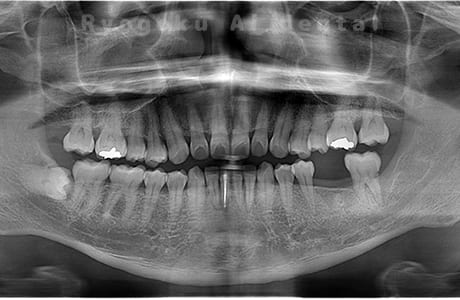

Case07

- 原因

- 右下6番歯根破折

-

- 治療内容

- インプラント治療

- 治療費用

- 約600,000円

右下の腫れが治らないとの事でご来院された患者様です。歯が割れていたため、抜歯を行い、骨に代わるお薬を入れ、インプラントを埋入致しました。経過良好で大変満足していただけました。

<リスク・副作用>

治療後、痛みや違和感、出血、腫れなどが出る事があります。喫煙者、糖尿病などの方の場合、歯が生着しない場合があります。